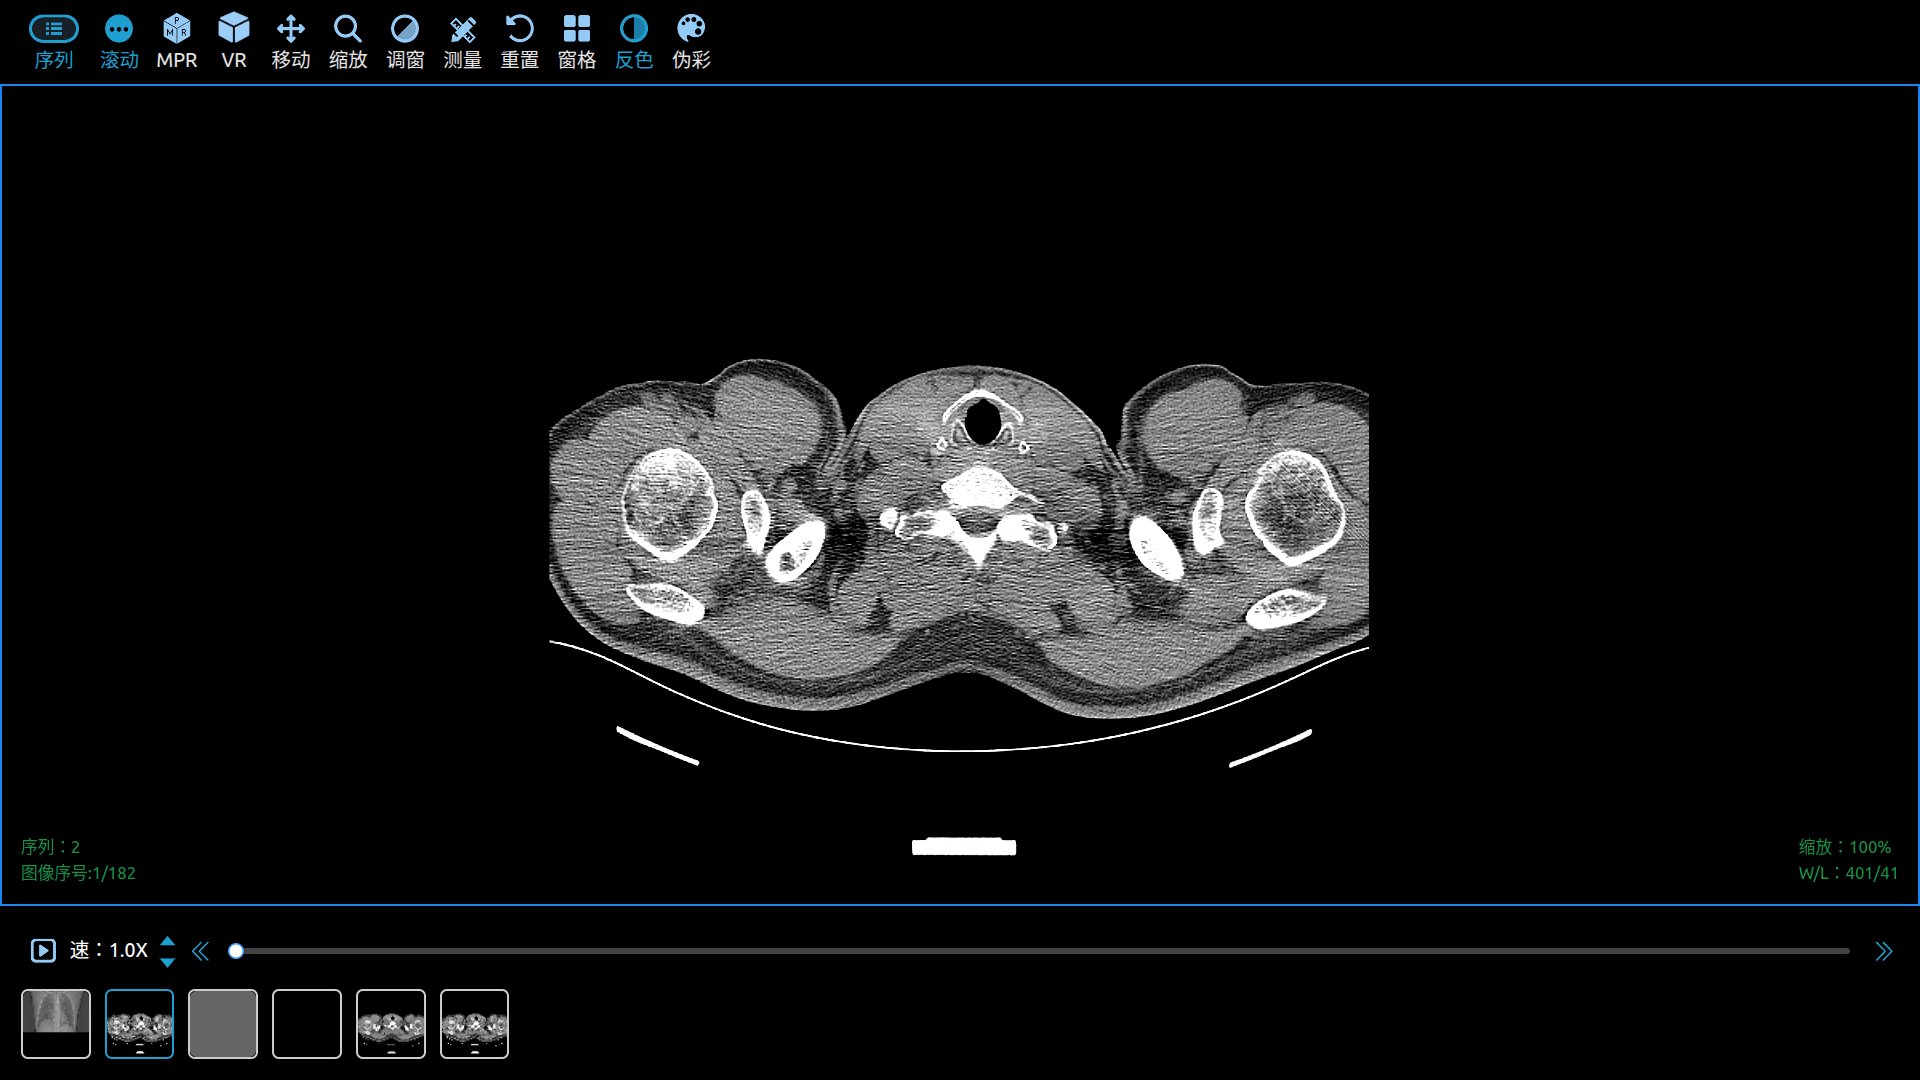

Use Cornerstone3D to View DICOM Images in a Web Browser.